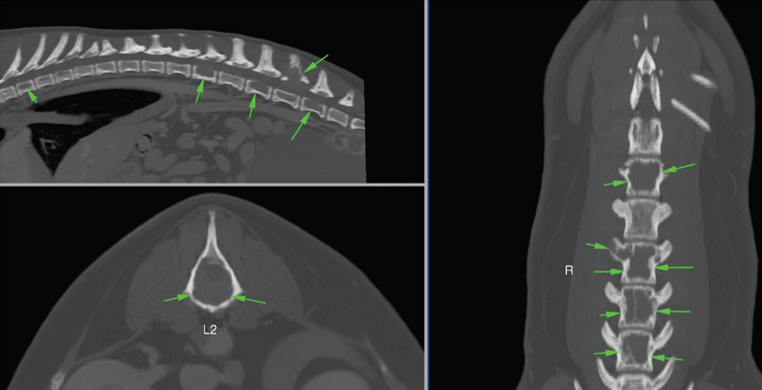

Our diagnostic imaging team performed a CT s scan of Kimba’s spine under anaesthesia (see pictures below) which showed multiple aggressive osteolytic lesions (bone destruction) affecting the lumbar and thoracic vertebrae in the spine, with associated soft tissue mass lesions. These results indicated that cancer was the most likely cause of Kimba’s high blood calcium. Consequently, the cancer was destroying the bones, causing pain, and pressing on the spine, causing wobbliness: there was moderate to marked compression of the spinal cord.

Figure 1: Sagittal, transverse and dorsal MPR MIP images showing polyostotic osteolytic vertebral lesions (arrows)

Figure 2A: Sagittal, transverse and dorsal MPR MIP images showing contrast-enhancing soft-tissue masses at the sites of the osteolysis. At L2, the contrast-enhancing soft tissue mass (green arrows) caused compression of the spinal cord (red arrows).